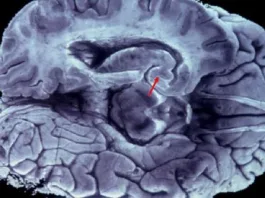

Ο άνθρωπος που πέθανε πριν 2.400 και μοιάζει ζωντανός – Ποιος...